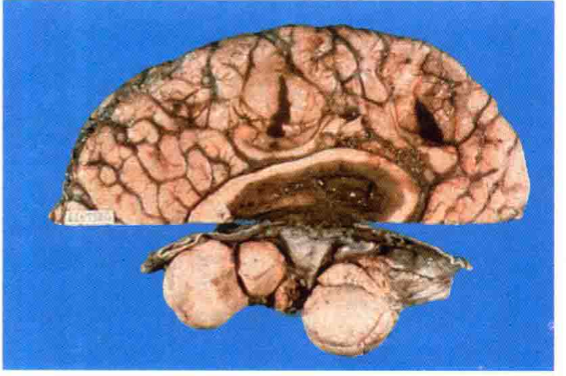

脑脊液量增多伴脑室扩张称为脑积水。脑积水发生的主要原因是脑脊液循环的通路被阻断。引起脑脊液循环受阻的原因很多,诸如先天畸形、炎症、外伤、肿瘤、蛛网膜下腔出血等。脑室内通路阻塞引起的脑积水称阻塞性或非交通性脑积水,表现为部分脑室的扩张;如脑室内通畅而因蛛网膜颗粒或绒毛吸收脑脊液障碍所致的脑积水称交通性脑积水。此外脉络丛乳头状瘤分泌过多脑脊液也可导致脑积水,常表现为全脑室的扩张。